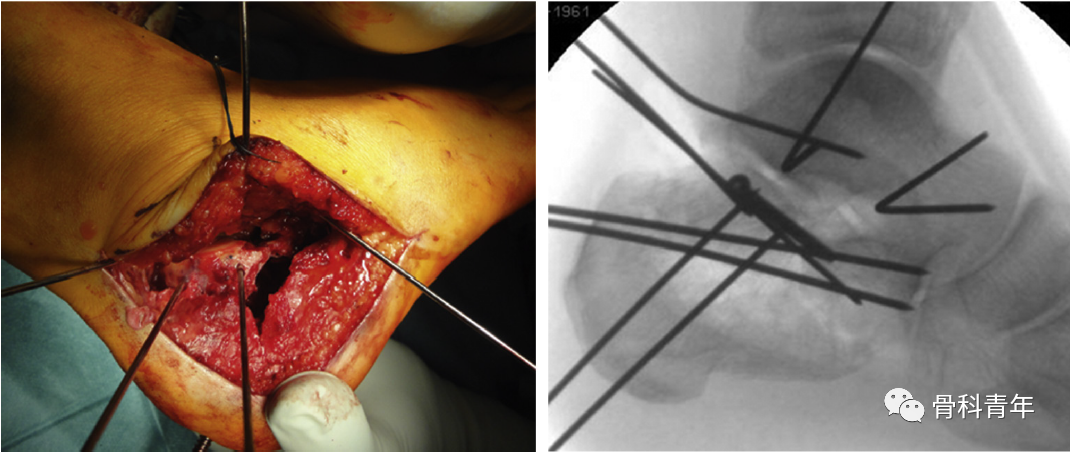

2. “不接触”技术牵开皮瓣“不接触”技术通常采用4枚1.6mm克氏针,分别固定在:

① 腓骨远端;牵引皮瓣近端;② 距骨颈;牵开肌腱与皮瓣中间部分;③ 骰骨;牵开肌腱远端部分;④ 距骨体;有助于暴露后关节面。弯曲克氏针使皮瓣回缩,在后续手术操作过程中,无需触及皮瓣。

3. 骨折复位与固定皮瓣掀开后暴露跟骨外侧壁,此时跟骨外侧壁可能阻挡骨折复位及骨折线的观察,将外侧壁骨块取出;

将4.5mm斯氏针置入后外侧骨块,操作骨折块复位;将跟骨结节骨折块复位与载距突上,纠正内翻,恢复高度。并沿足底穿入克氏针临时固定。

将骨膜剥离子插入塌陷后关节面下方,撬拨复位。

克氏针临时固定复位的关节面,此时后关节面复位后如存在较大缺损,则需植骨;

透视侧位接骨板位置,首先固定钢板前上方的螺钉,后术者用拇指下压接骨板恢复跟骨宽度,中指和环指纠正内翻。